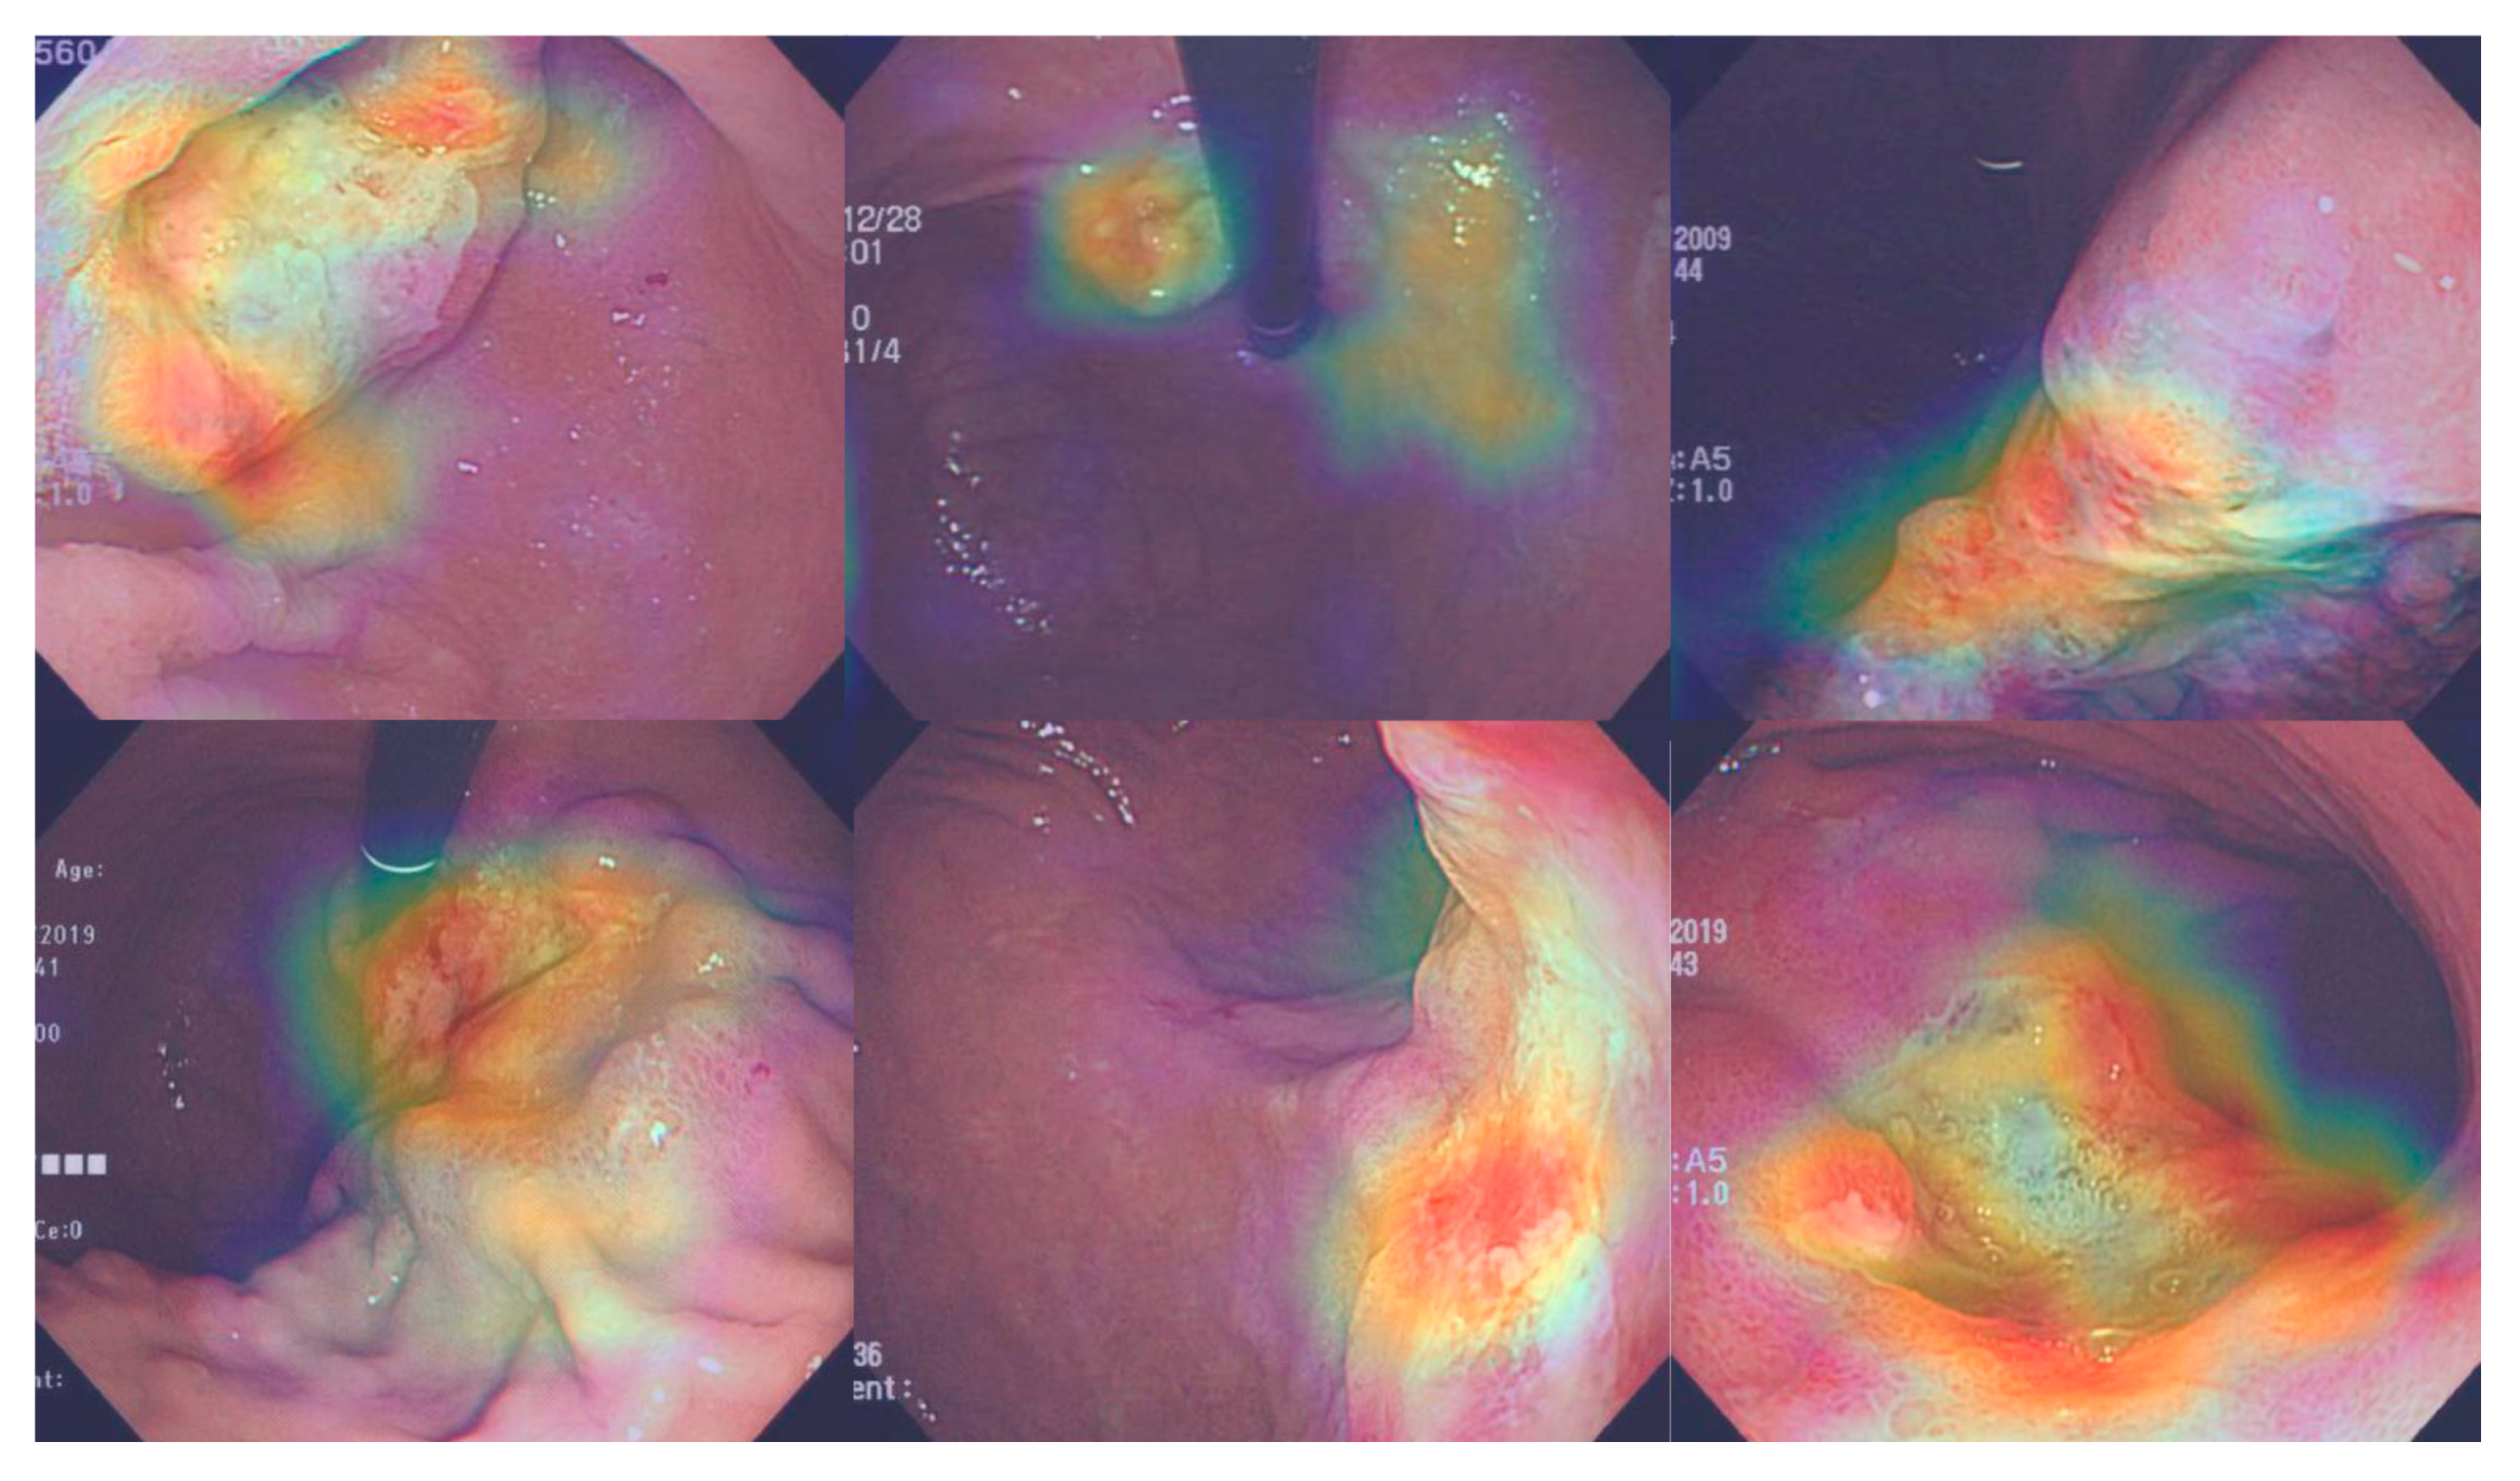

3.5. Attention Maps